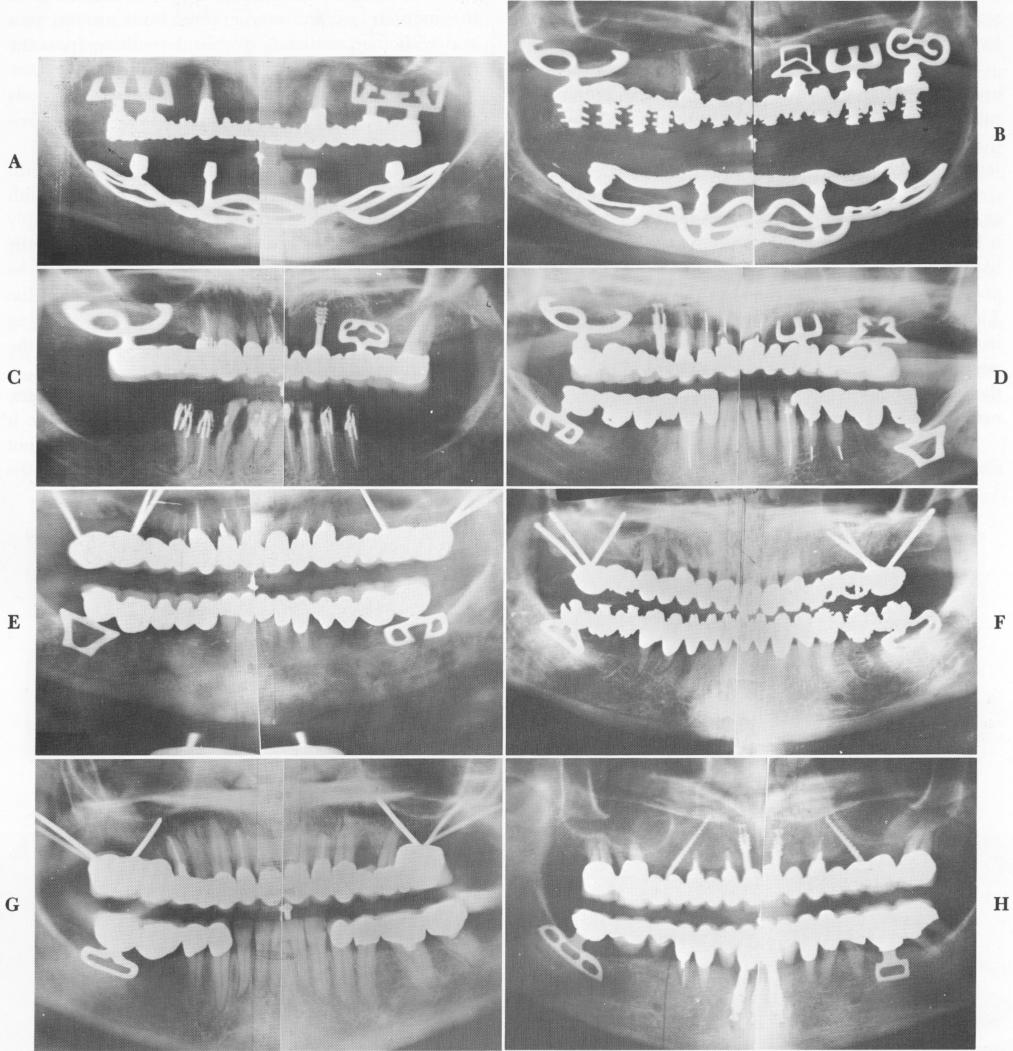

472 Theories and techniques of oral implantology

Fig. 11-25. A and B, Two cases showing blades used with other types of implants in the maxilla with opposing subperiosteal mandibular implants. (From Linkow, L. I.: The blade vent, a new dimension in endosseous implantology, Dent. Concepts 11:3-18, 1968.) C and D, Mixed mandibular and maxillary endosseous implants. (From Linkow, L. I.: The endosseous blade, a new dimension in oral implantology, Rev. Trim. Implant., Nov., 1968.) E to G, Blades in the mandible opposing tripods in the maxilla. H, Mandibular blades and vent-plants opposing narrow-ridge implants and vent-plants. (From Linkow, L. I., and Weiss, J. L.: The endosseous blade: a progress report, Prom. Dent., No. 5, 1969.)